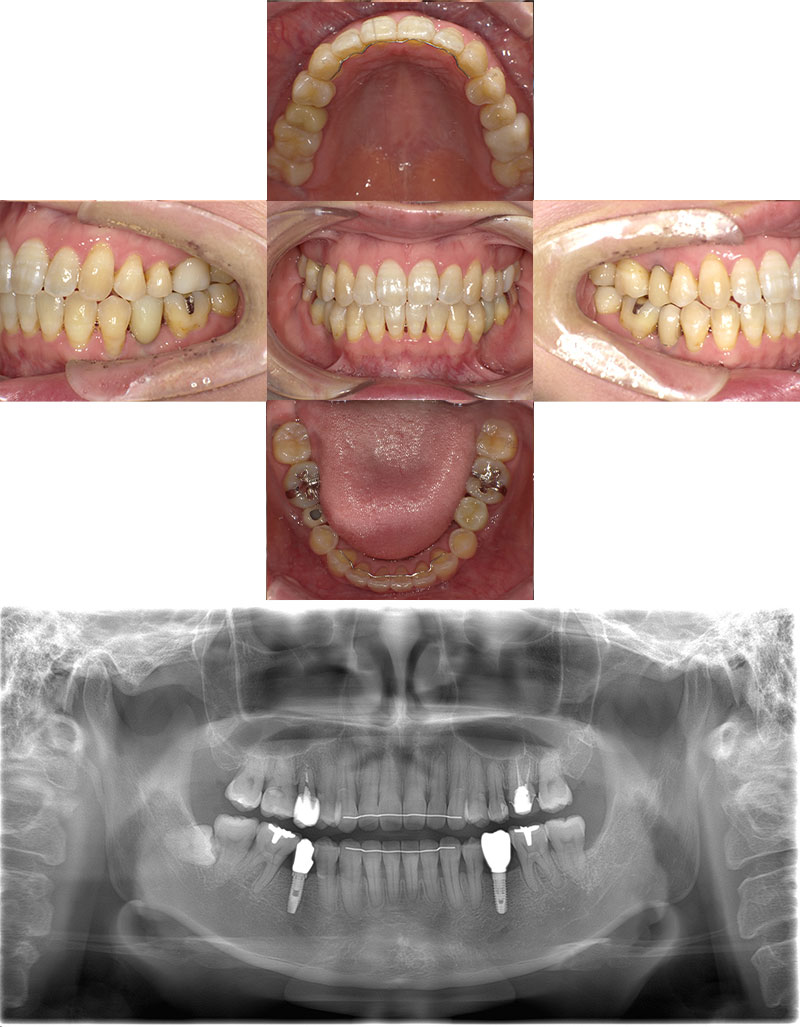

ワイヤー矯正+インプラント症例

治療前

Before

治療後

After

年齢 43歳

性別 女性

主訴 左下の乳歯を抜きたい